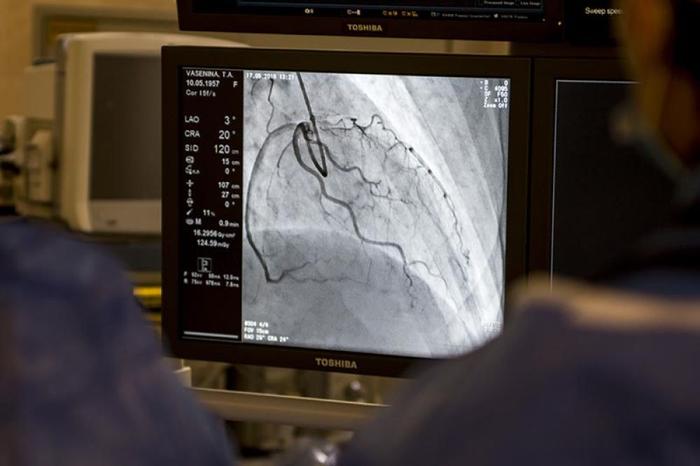

С помощью контраста и рентгеновского аппарата на экране отображается изображение сосудов, что позволяет врачу тщательно аналировать участки сужения артерий и степень их заболеваемости. Чаще всего коронарография не требует общего наркоза, обычно достаточно местной анестезии. Это исследование не требует длительной госпитализации и обладает высокой диагностической ценностью для оценки здоровья пациента, разработки лечебных мероприятий и определения объема хирургического вмешательства.

Ангиограф – это рентгеновский аппарат, предназначенный для проведения исследований и процедур с использованием рентгеновского излучения и контрастного материала. В операционной, оснащенной ангиографом, мы можем не только проводить диагностику сосудистых поражений, но и осуществлять терапию.

Контрастные вещества «окрашивают» коронарные артерии, позволяя визуализировать их внутреннюю структуру на ангиографе. В нашей практике применяются контрастные препараты на основе неионного йода. Мы используем только современными и безопасными для здоровья контрастные вещества.